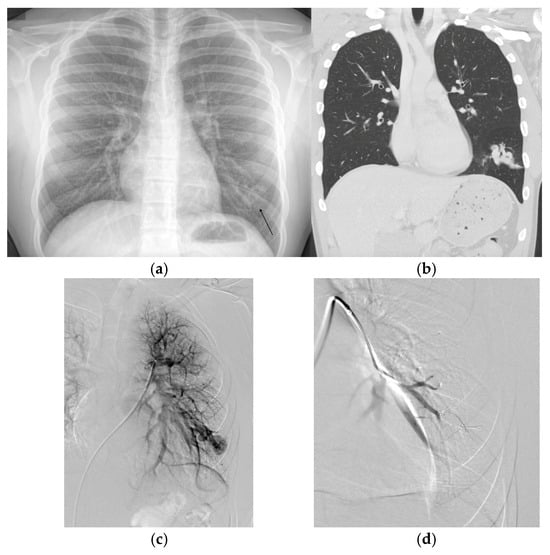

3.3. Angiography

4.2.1. Embolotherapy